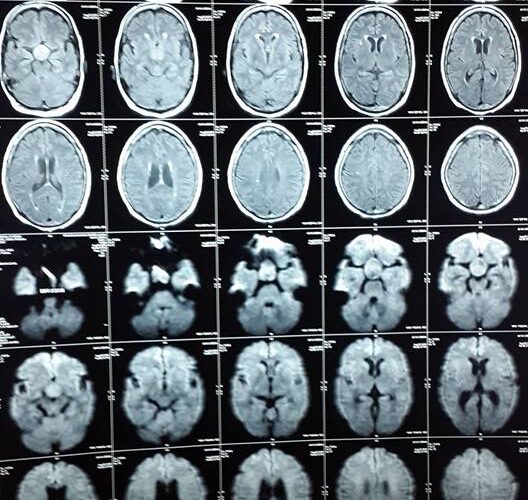

3 Endoscopic Pituitary Cases in Manik Hospital